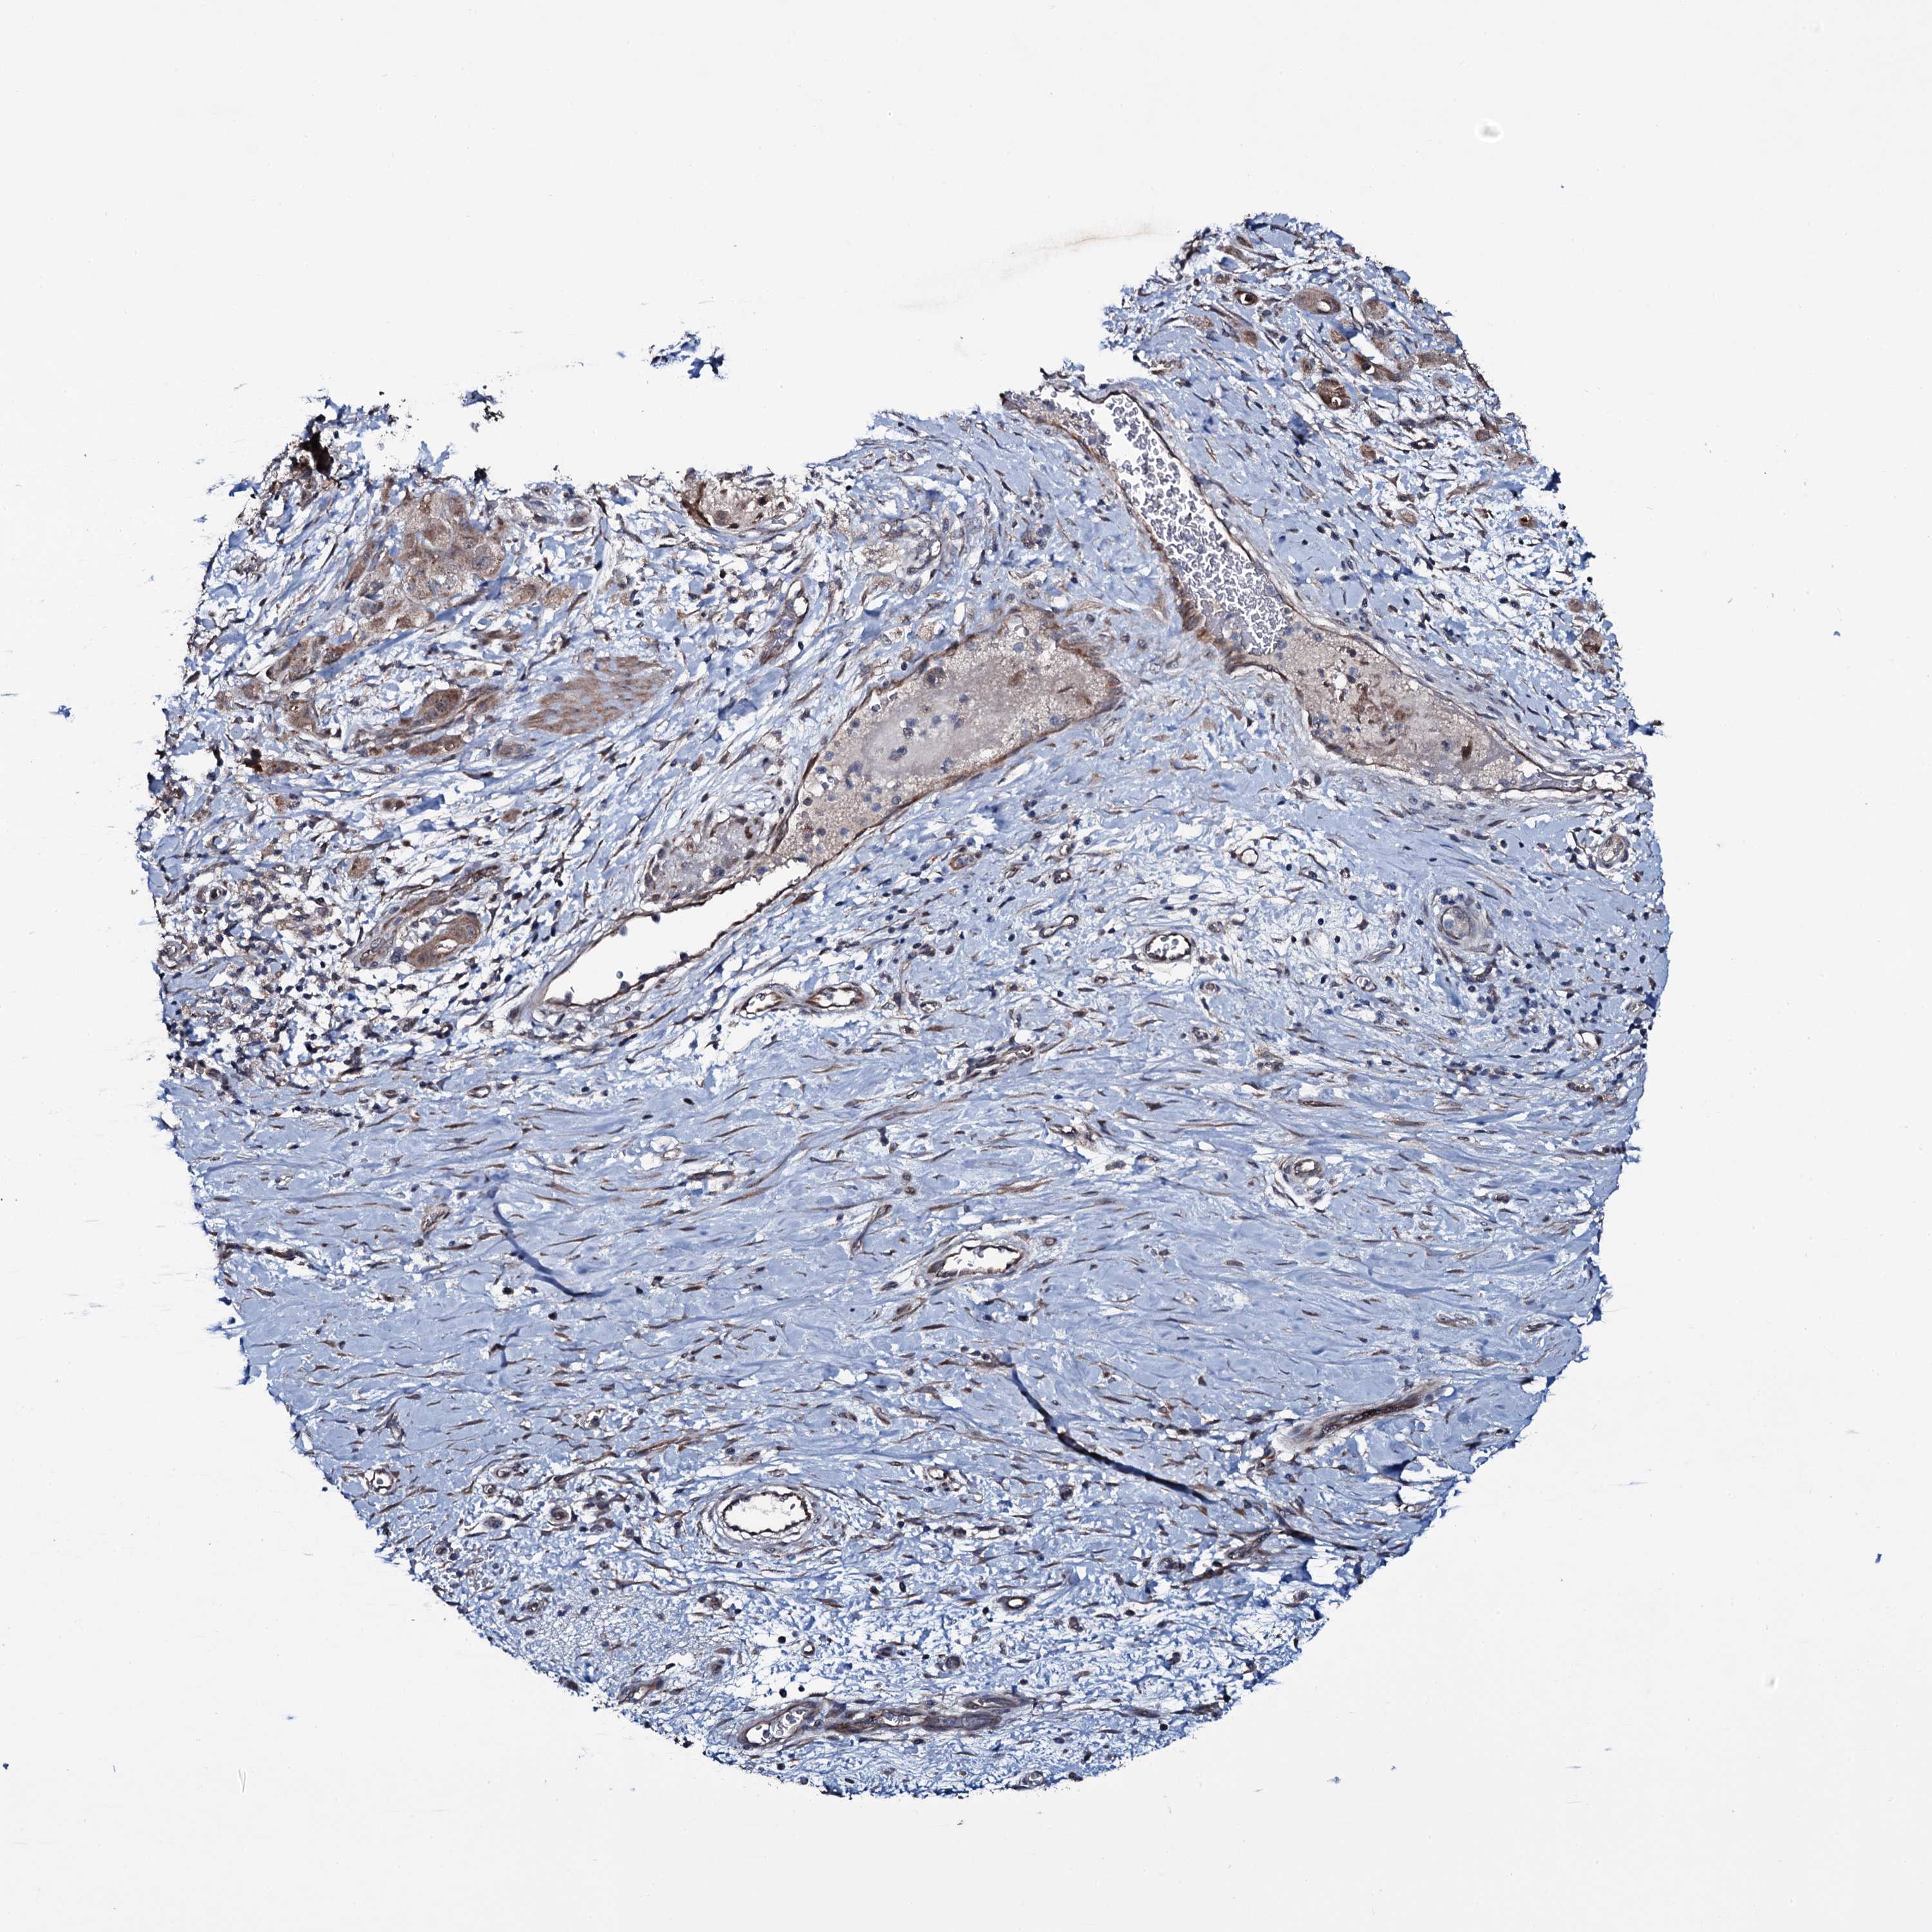

STOMACH CANCER - Protein expressioni

A mouse-over function shows sample information and annotation data. Click on an image to view it in a full screen mode. Samples can be filtered based on level of antibody staining by selecting one or several of the following categories: high, medium, low and not detected. The assay and annotation is described here.

Note that samples used for immunohistochemistry by the Human Protein Atlas do not correspond to samples in the TCGA dataset.

Antibody stainingi

Antibody staining in the annotated cell types in the current human tissue is reported as not detected, low, medium, or high, based on conventional immunohistochemistry profiling in selected tissues. This score is based on the combination of the staining intensity and fraction of stained cells.

Each image is clickable and will lead to virtual microscopy that enables deeper exploration of all samples and also displays staining intensity scores, fraction scores and subcellular localization as well as patient and tissue information for each sample.

Antibody HPA039083

Antibody HPA046344

Staining

High

Medium

Low

Not detected

Intensity

Strong

Moderate

Weak

Negative

Quantity

>75%

75%-25%

<25%

None

Location

Nuclear

Cytoplasmic/membranous

Cytoplasmic/membranous,nuclear

Adenocarcinoma, NOS

Adenocarcinoma, High grade